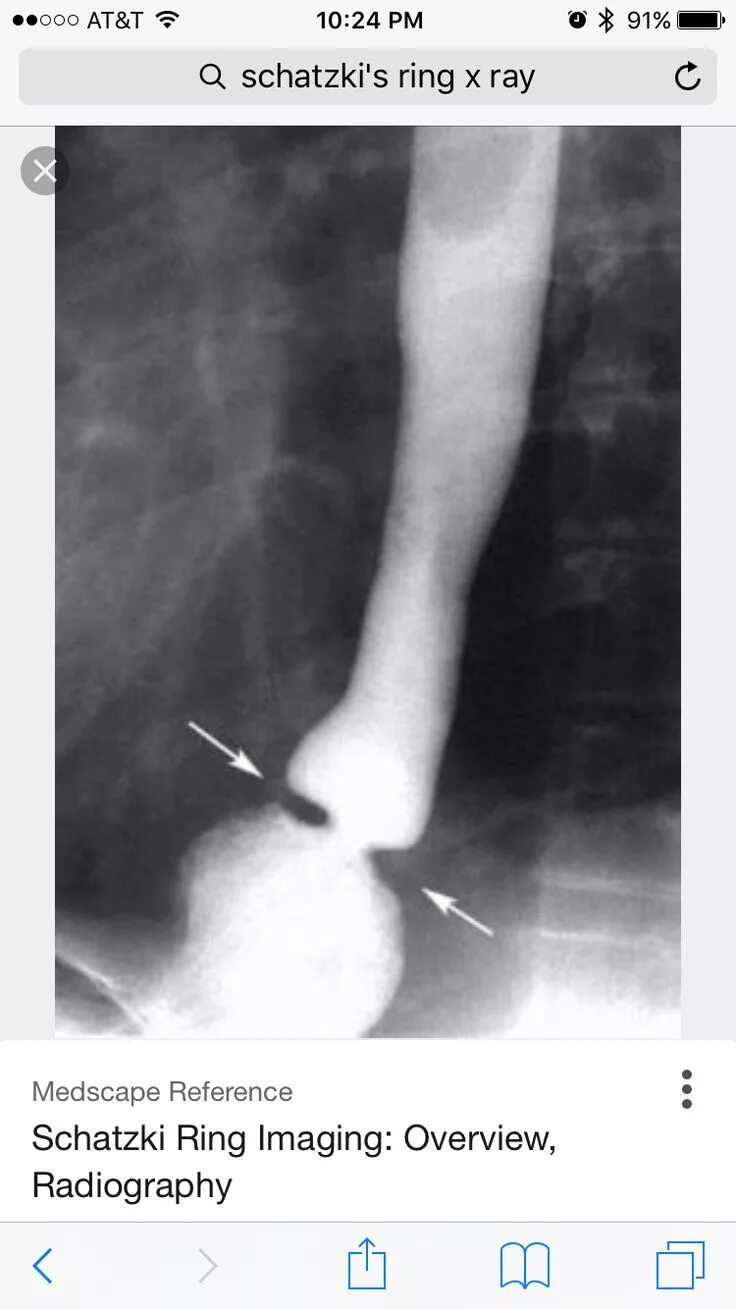

Кольцо шацкого в пищеводе что это